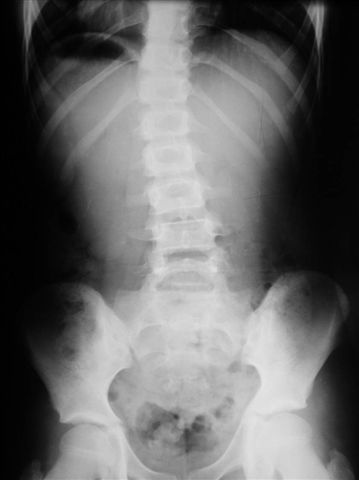

Na radiogramach przebieg leczenia jednej z moich pacjentek.